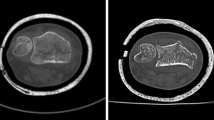

Forearm specimens were thawed for 24 h at 4 °C. Radii were extracted using a modified Henry approach, whereby all ligaments, the interosseus membrane, and the articular capsule were incised. Care was taken to minimize damage to surrounding soft tissue, as the forearm specimens were used to re-implant the radii following their fracture simulation. The explanted radii were macerated in water for two weeks at 60 °C to fully remove soft tissue. Specimen-specific osteotomy guides were designed in Mimics Research (V21.0; Materialise NV, Leuven, Belgium) to enable defined cutting and tilting of the distal radius, to mimic a loco typico fracture. Hereby, the fracture line was defined as previously described by Baumbach et al. [35]. In brief, the authors determined the fracture location on the dorsal and palmar side from radiographs of 157 dorsally displaced distal radius fractures in relation to the corresponding apices of the lunar facet. According to existing literature [35,36,37,38], the average volar inclination of the distal radius is 11.0° in its anatomic position, whereas Baumbach et al. [35] measured a volar inclination of -15.1° on dorsally displaced distal radius fractures. Hence, in the present study, the osteotomy guides were designed to enable a defined dorsal tilting of the distal fracture fragment by 26.1° from its anatomical position. Figure 1 illustrates sequential steps of the procedure: First, the osteotomy was executed on the radius specimens with a buzz saw at the predefined location. Second, the osteotomy guide was cut to enable its manipulation and dorsal inclination of the distal fracture fragment. The fracture fragment was secured by inserting and affixing a wedge into the fracture gap with super glue (Loctite 1,462,904, Henkel AG & Co. KGaA, Düsseldorf, Germany). The wedge, composedof five epoxy glass fiber plates milled using computerized numerical control (CNC), was affixed in a staggered arrangement. Precise positioning was achieved by incorporating two 6.0 mm fitting dowel pins (see inset in Fig. 1). Pilot CT scans confirmed the distinct contrast between epoxy glass fiber plates and bone tissue, facilitating their straightforward isolation in image-processing.

3D Surface Scanning

The surfaces of the fractured radius specimens underwent scanning using a high-resolution 3D scanning system (SmartSCAN HE-C8-8MP, Hexagon AB, Stockholm, Sweden; field of view: 250 mm, resolution: 64 μm (x and y direction), feature accuracy: 14 μm). Given the high resolution, 3D computer-aided design (CAD) models, generated from the surface scans, served as the ground truth for determining the dimensional accuracy of the CT-based 3D models. As radius specimens exhibited porosities on the surface and a thin shell in the epiphysis, a white powder (Crick 130, CRC 20,790-AJ, CRC Industries, Horsham Township, Pennsylvania, USA) was applied to enhance surface quality during scanning. The resulting surface models were exported as standard triangle language (STL) files and imported into 3-matic Research (V 13.0; Materialise NV, Leuven, Belgium). The epoxy glass wedge was manually removed and distinct epiphyseal and diaphyseal parts were created using the “trim” tool (in the following referred as surface scan models).